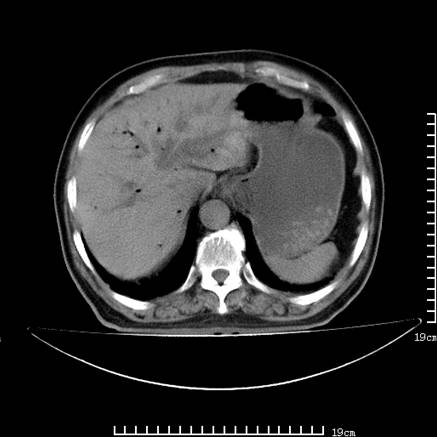

以下是引用lirenxiong在2008-7-19 22:01:00的发言:[br]胆总管结石并胆系感染,胆囊切除术后改变!左肾未见!左肾上腺增生肥大?请全腹扫描,增强!

以下是引用lirenxiong在2008-7-19 22:01:00的发言:[br]胆总管结石并胆系感染,胆囊切除术后改变!左肾未见!左肾上腺增生肥大?增强!